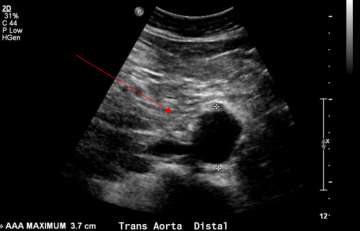

Ultrasound image of AAA detected by screening, measuring 3.7 cm (red arrow)

Ultrasound image of AAA detected by screening, measuring 3.7 cm (red arrow).